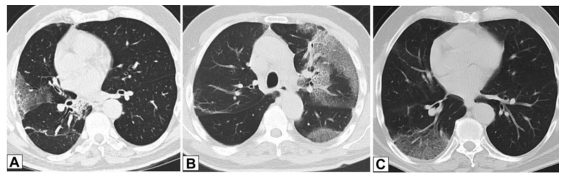

图源:Chest, 2022, 162(1):156-178.CT扫描图像显示双肺多发小实性结节(图8),提示恶性肿瘤或感染可能。CT扫描引导下针吸活检结果与OP诊断一致。图源:Chest, 2022, 162(1):156-178.42岁患者,病态肥胖,有呼吸困难,右肺上叶(图9A)和右肺下叶(图9B)CT平扫图像显示双侧、胸膜下或周围肿块样实变区域。这些发现为非特异性;活检结果提示OP,类固醇治疗后消退。图源:Chest, 2022, 162(1):156-178.OP以结节为主的影像学表现,范围从小的微结节(直径<4 mm)到较大的离散结节(直径通常达1 cm),以及较大的结节或肿块。较大的结节或肿块常被描述为具有不规则或锐利边缘,通常包含支气管充气征。图10所示为一名接受美沙拉嗪治疗的38岁男性溃疡性结肠炎患者出现气促。A为后外侧胸片,显示双肺多发结节。胸部CT增强扫描显示结节为周围型和支气管血管周围型,一些伴有气道扩张(B和C中的箭头)。粗针穿刺活检结果与OP相符。图源:Chest, 2022, 162(1):156-178.此外,结节可以单发或多发,通常为实性结节或部分实性结节。图11为一名73岁男性吸烟者低剂量CT,CT平扫图像显示右肺上叶孤立的不规则结节影,伴有细微的气道扩张(A中箭头)。支气管内超声引导下细针活检结果符合局灶性OP表现。图源:Chest, 2022, 162(1):156-178.临床中遇到影像学表现为结节的情况,需要注意与肿瘤相鉴别。PET扫描对这些病变的评估显示标准化摄取值轻微升高,但结果为非特异性,临床价值有限。图12所示为PET扫描一名无症状、有乳腺癌病史并长期使用呋喃妥因的70岁女性,CT平扫图像显示双肺下叶不规则、实性结节。由于担心转移性疾病,进行了PET扫描(图12C),轴位PET图像显示左肺下叶结节(B、C中箭头)是FDG高摄取。左肺下叶结节的粗针穿刺活检结果与OP相符。图源:Chest, 2022, 162(1):156-178.34岁女性患者因系统性红斑狼疮就诊,表现为气促。胸部CT显示双肺多发大小不等的实性结节,包括左肺基底部微小结节改变(图13A)。FDG-PET扫描的图像显示结节为高代谢(图13B)。两个结节的楔形活检结果符合OP诊断。图源:Chest, 2022, 162(1):156-178.以线状或网状为主的OP影像特点包括表现为线状不透明的实质条带,通常延伸到胸膜表面,先于磨玻璃影或实变。图14所示为条带活检证实为OP的同一患者间隔1年进行的CT扫描,可见患者双肺下叶条带部分消退(A、B中箭头)。